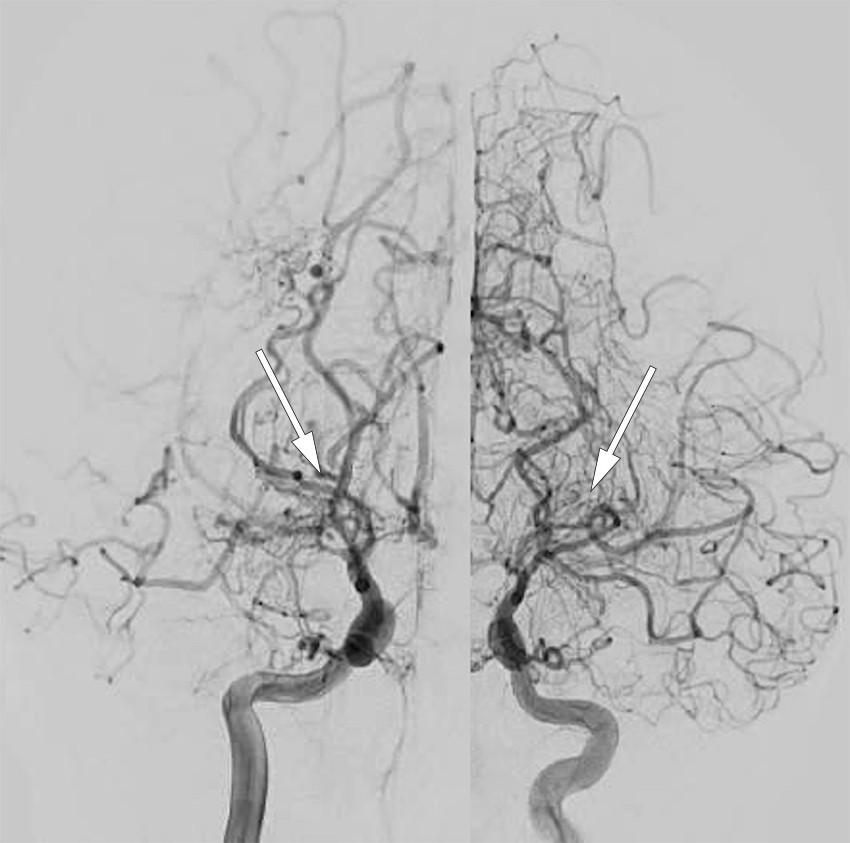

Direkte revaskularisering er en mikrokirurgisk ekstrakranial–intrakranial bypass med lav blodstrøm (low-flow), typisk mellom en frontal eller parietal (eller begge) gren av a. temporalis superficialis og en tilstrekkelig stor kortikal gren av a. cerebri media. Til tross for at et det er et lite kaliber på blodårene som sys sammen, er det påvist en rask økning av blodgjennomstrømningen i området etter prosedyren, og risikoen for blødning blir redusert (14, 15).

Ved indirekte revaskularisering benyttes et rikt vaskularisert vev i anatomiske lag over hjernen. Det finnes flere tekniske modifikasjoner (7, 16). Det mest fullstendige er encefalo-duro-arterio-myo-synangiose, der dura mater med a. meningica media samt periost og temporalmuskel legges direkte på hjernens overflate, hvilket fører til neovaskularisering, dvs. innvekst av nydannede kapillarer inn i hjernen. Ulempen er et lengre tidsintervall til utvikling av klinisk effektiv revaskularisering. Metoden har likevel vist seg å være spesielt effektiv hos barn og er derfor ofte benyttet (17), særlig der direkte bypass er teknisk utfordrende. Ved en eventuell reoperasjon kan man benytte seg av en relativt enkel metode, hvor det lages flere trepanasjonshull over et affisert område av hjernen og små lapper av periost legges på hjernen gjennom disse hullene (18).

Kombinert revaskularisering innebærer både direkte bypass samtidig med indirekte revaskularisering (19). Denne kombinasjonen benyttes særlig ofte hos barn der det er mulig (figur 3).